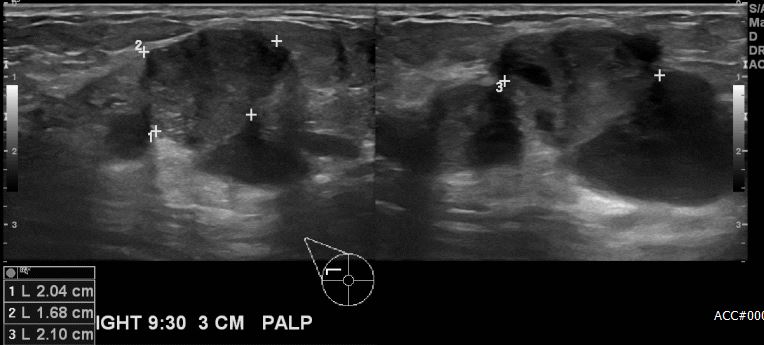

상기환자 우측 유방의멍울로 내원하신 60대 여성분으로 우측 9시30분 방향에서 3cm 떨어진 거리의 만져지는 멍울 조직검사 시행하여 우측 침윤성 유관암 진단 되었습니다.